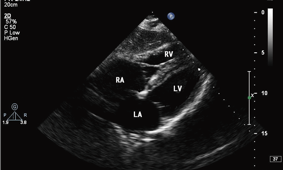

影像诊断

心电图 / 心脏彩超 /心血管造影影像 / …

远程协诊远程会诊...